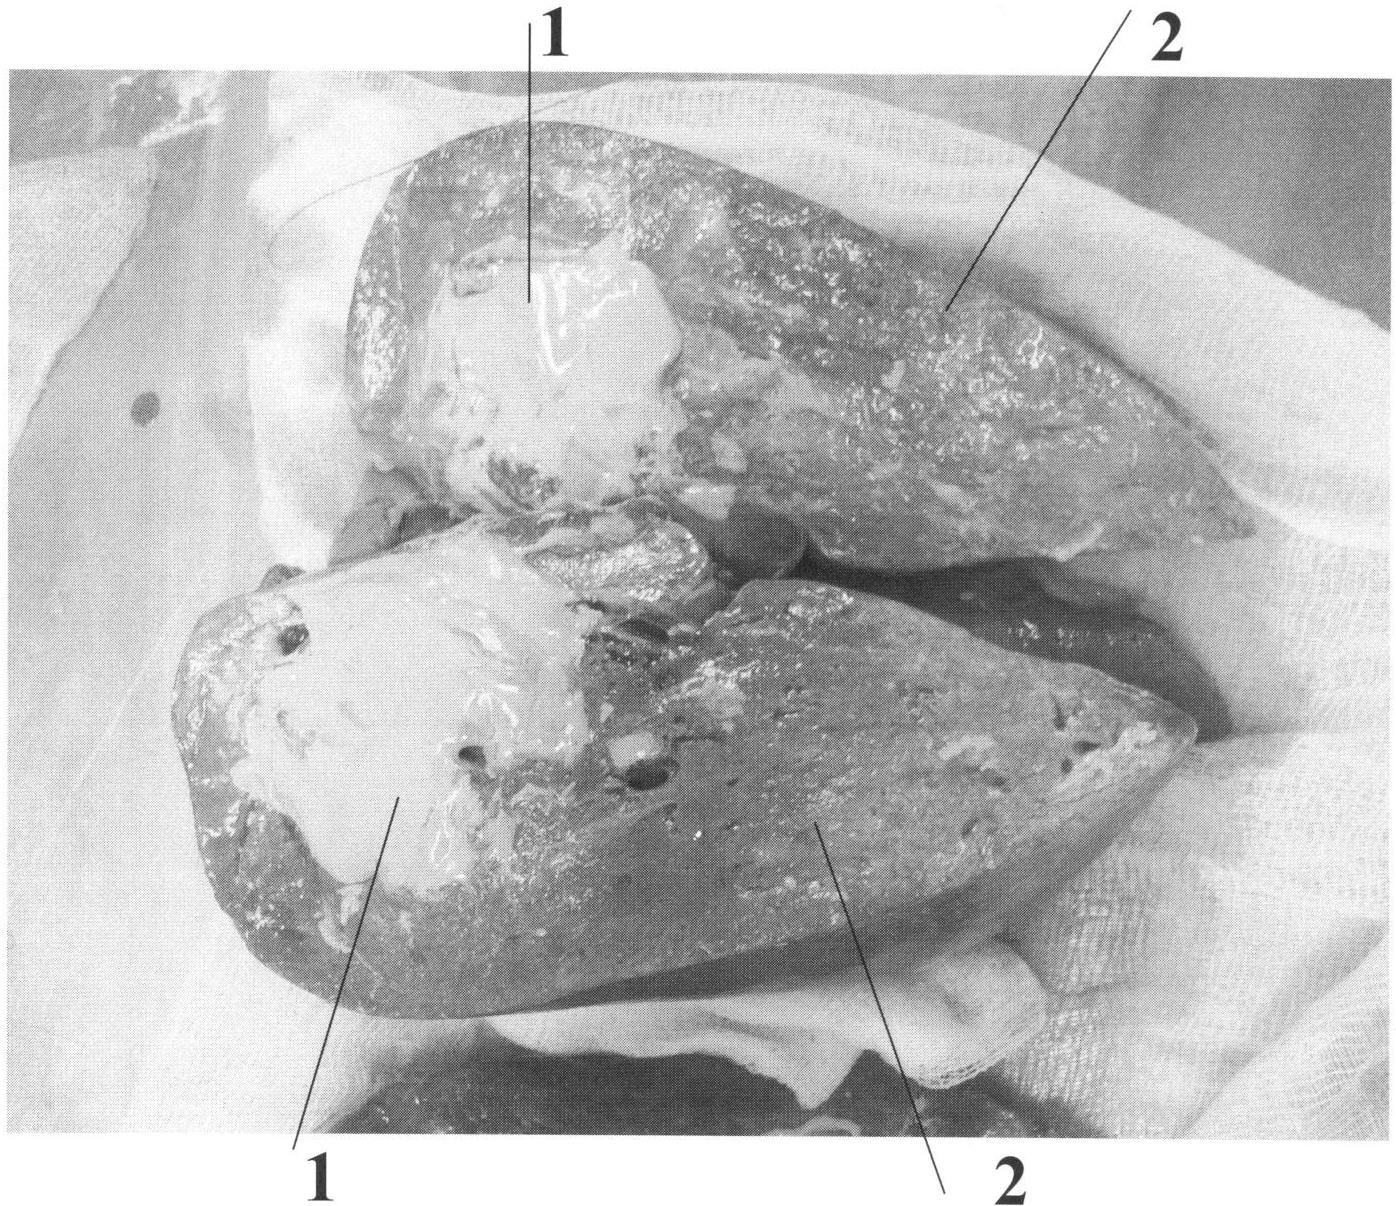

Для реализации заявленного способа использовали трупный препарат печени внезапно умершего человека с отсутствующей патологией печени, сохраненный в электрохолодильном шкафу при температуре +4 градуса Цельсия в течение не более 24 часов. В паренхиме трупного препарата печени иссекают капсулу диаметром 5-6 мм, в нее тупым путем вводят трубку из латекса на глубину 3-4 см. К трубке присоединяют флакон с монтажной пеной, которую вводят с быстрым удалением трубки. Места прокола придерживают мокрым тампоном, смоченным в холодной воде, предотвращая выход введенной пены. Модели, созданные таким образом на 5 препаратах, исследовали на предмет изучения сосудистой архитектоники методом зондирования и селективной ангиографии печеночных вен и их ветвей. Полученные изображения вполне отчетливо показывают, каким образом изменяется направление сосудов при очаговых объемных заболеваниях печени. Полученная экспериментальная модель «опухоли» печени оказалась крайне удобной для освоения хирургами техники резекции печени при очаговых поражениях магистральных сосудов печени и нижней полой вены. Модель представлена на фотографии препарата правой доли печени с опухолью 1, моделированной монтажной пеной, введенной в трупный препарат печени 2 человека (чертеж).